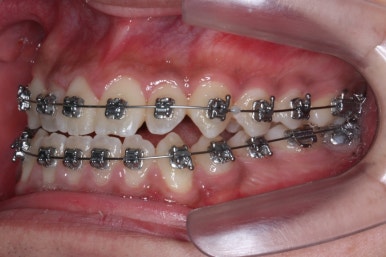

위 사진들은 부산주걱턱교정 키다리아저씨치과에 내원하셨을 당시의 입안 모습입니다.

입 안의 모습에서도 주걱턱의 특징으로는

하악이 앞으로 나와있습니다.

윗니는 뻐드러지고 아래 앞니는 뒤쪽으로 쓰러져 있습니다.

교합이 맞지 않습니다.

부산주걱턱교정 키다리아저씨치과에서 장치를 부착하였습니다.

이번에 사용된 장치는 자가결찰 메탈이며 가장 부피도 작고 튼튼하고 여러 장점이 있습니다.

점점 수술전 교정이 진행되는 모습입니다.

각각의 위턱과 아래턱뼈 제위치에 맞게 윗니는 뒤로, 아랫니는 앞으로 내어주게 됩니다. 수술직전까지는 어떻게 보면 교합은 점점 나빠진다고 볼 수 있씁니다.